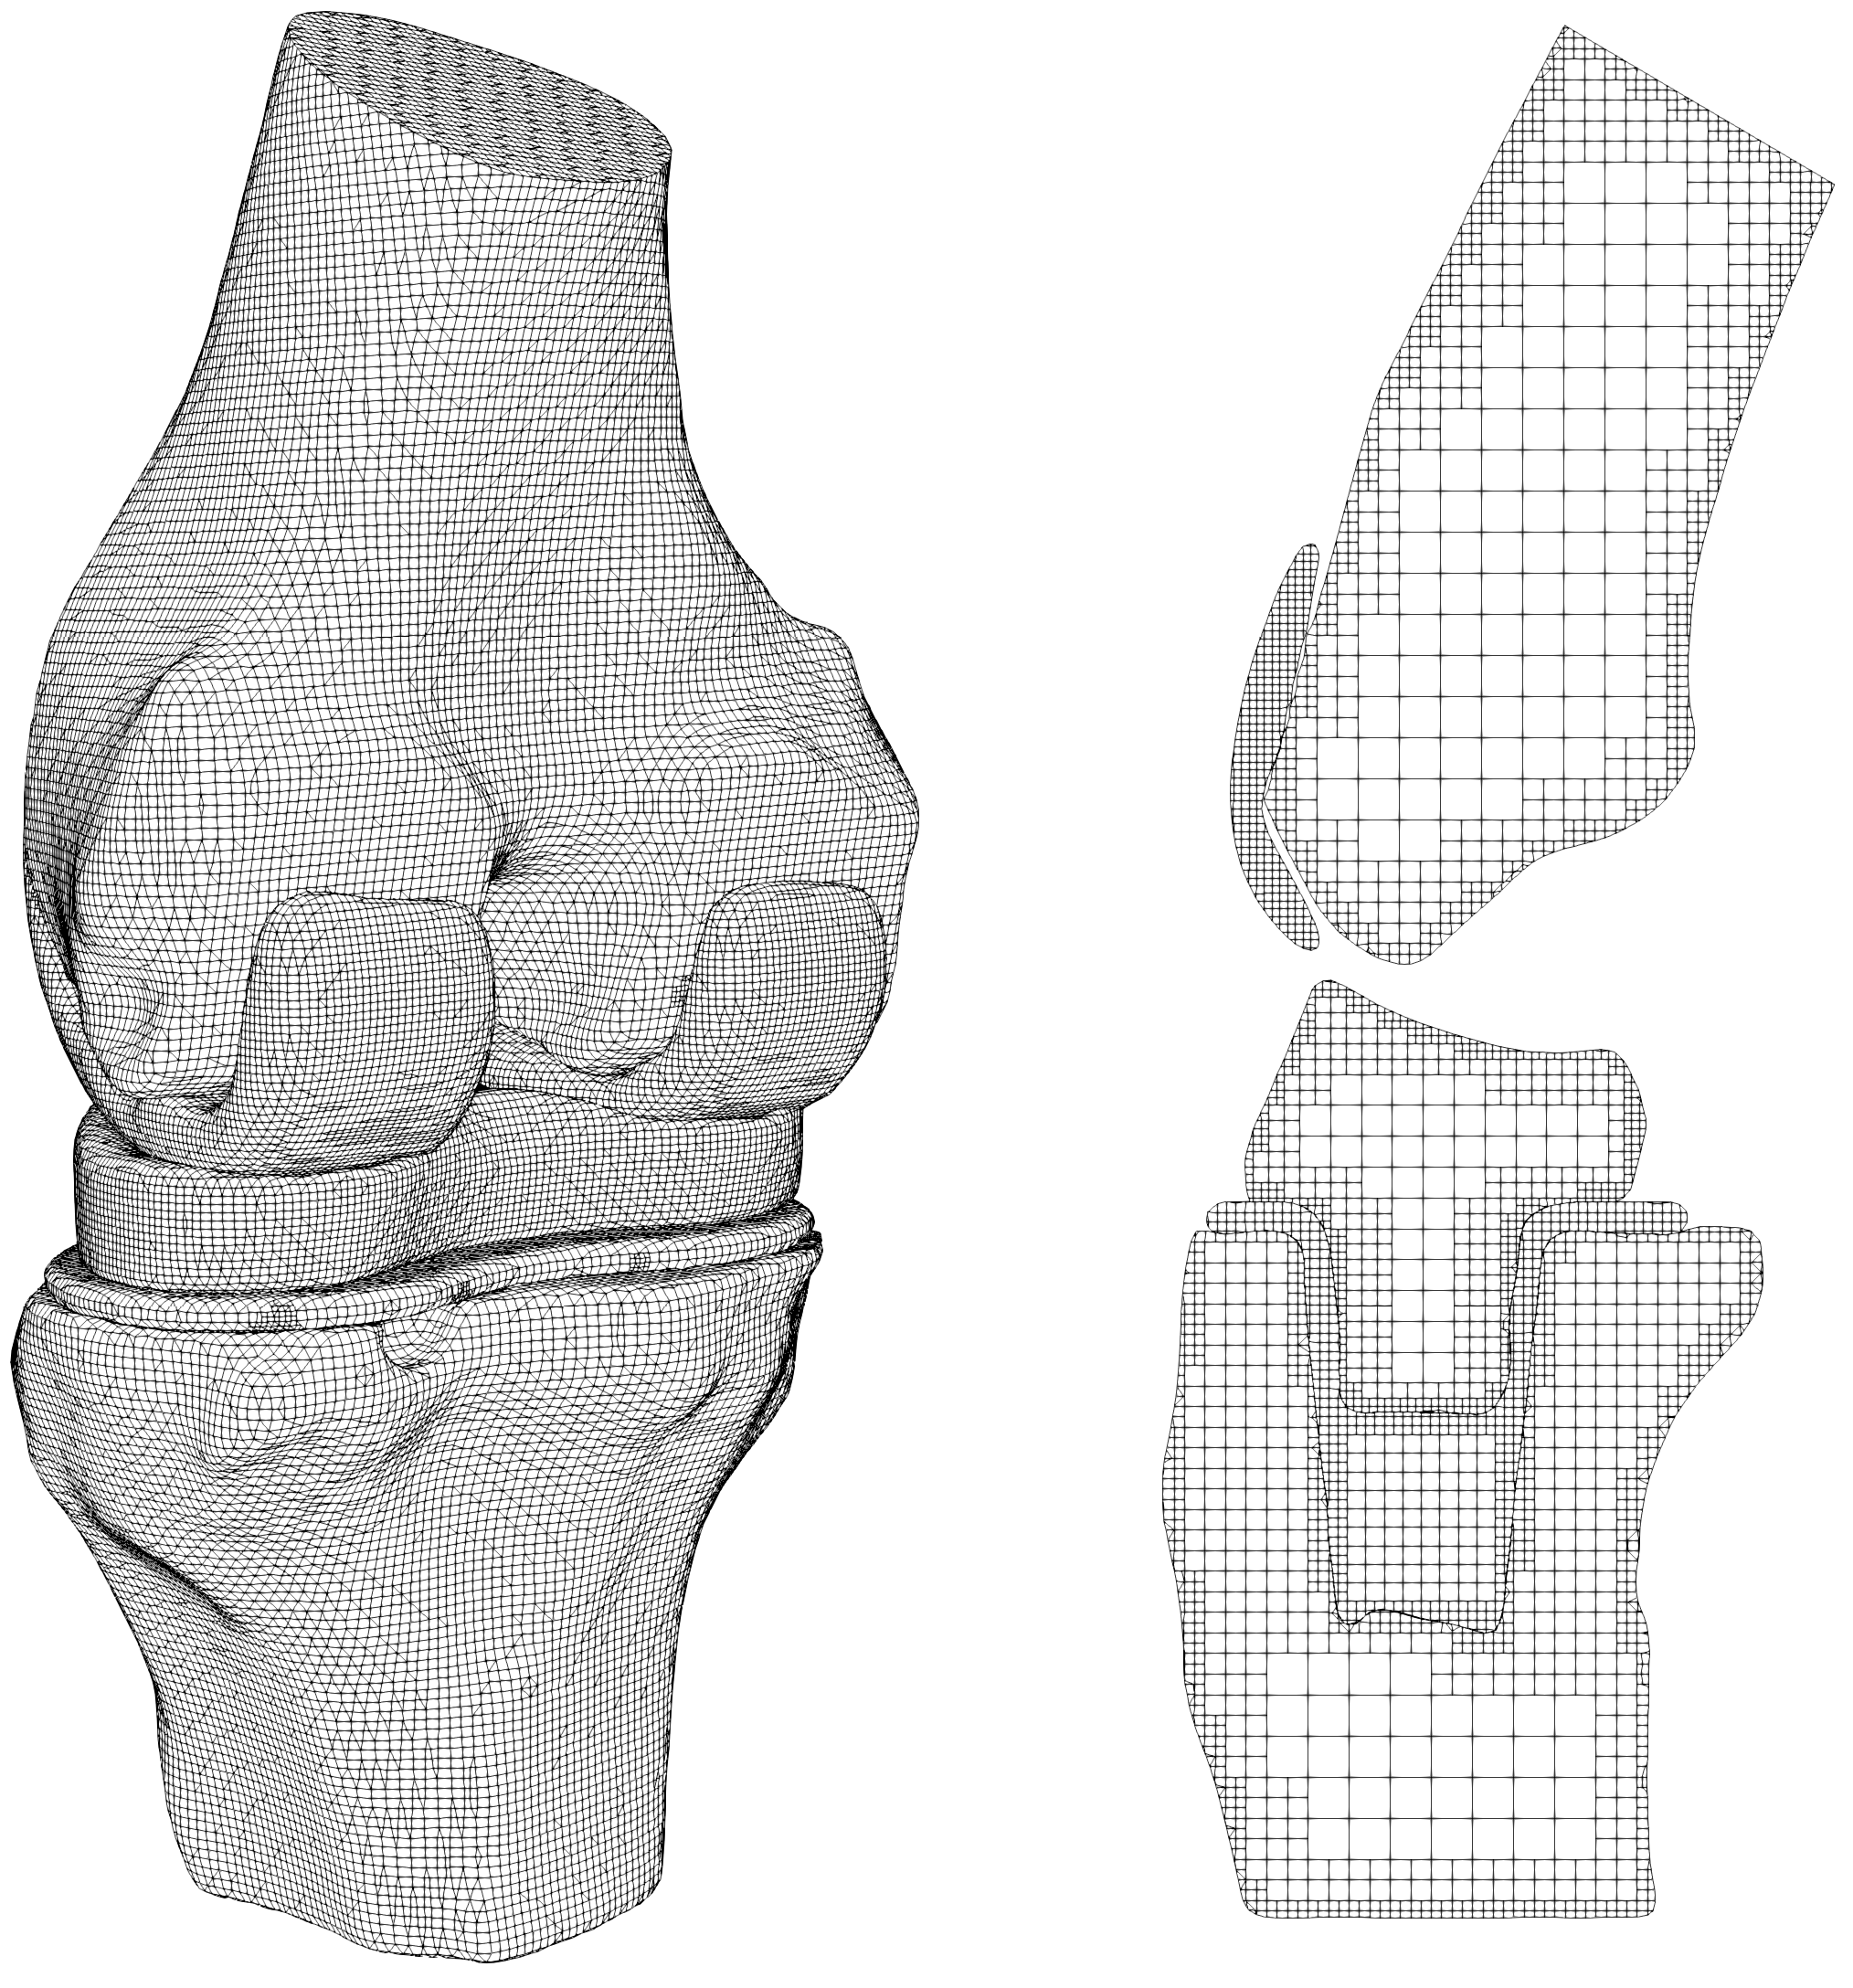

The mesh generated by the octree algorithm with trimming [29] is shown in Fig. 31. The base sizes are and for the contact parts and other parts, respectively. There are 253,079 elements and 361,296 nodes, and the number of nodes in one element varies from 4 to 27. A slice in the vertical plane passing the geometrical center is also shown in Fig. 31. The contact interface meshes are non-matching for this example, because the contact domains are geometrically non-conforming and large sliding might occurs at the interface during the loading process. The meshes generated through the STL-based octree algorithm are suitable for contact analysis. In the standard FEM, local mesh refinement may be required to generate finer meshes on the contact surfaces. However, in an automatic manner, octree cells with fast mesh size transition can be generated through the octree mesh generation technique. Compared to the interior elements, the elements near the boundaries are smaller, which will generate more accurate surfaces for tie constraints and contact pairs. Besides, compared to the image-based technique, the STL-based octree algorithm allows trimming on the octree cells, which leads to more accurate meshes representing complex boundaries especially for curved shapes.